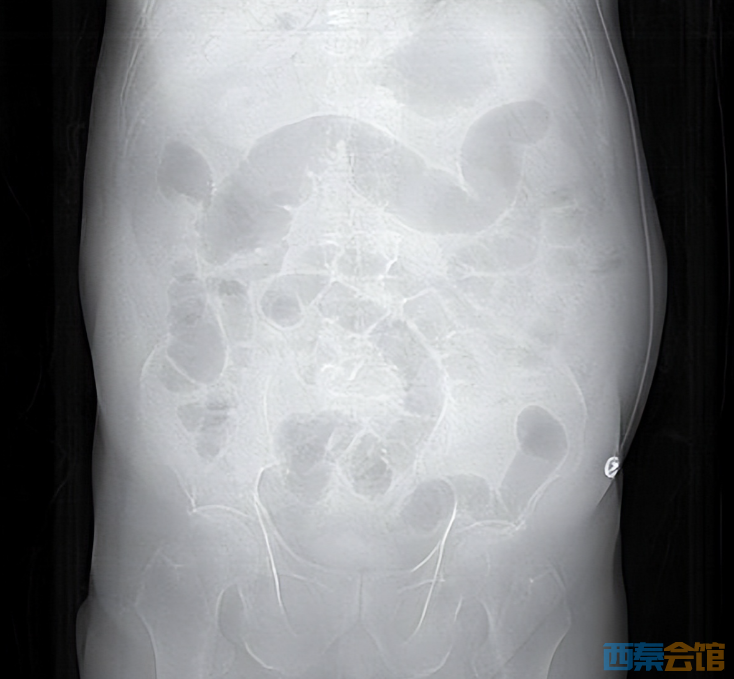

平时的剩菜、剩饭,一些人舍不得倒,习惯放冰箱里,到时候“热一热再吃”。但冰箱不是食物保险箱,食物保存不当或者放久了食用,会致病,甚至会危及生命。 近日,临海市第二人民医院ICU接诊一位76岁患者,只因吃了冰箱冷藏4天的鸡肉,突发休克、肝脏里布满气体,被医生判定为“死神之征”。 凶险急症: 肝门静脉积气 医学上的“死神之征” 当晚10点,76岁李大伯被家人紧急送入临海市第二人民医院急诊,他大汗淋漓、腹部僵硬如石。据家人说,李大伯从下午4点开始腹胀腹痛,症状持续加重。 急诊CT结果让医护人员高度警惕:肝门静脉及肠系膜静脉广泛积气。

肝脏内血管广泛积气

腹胀明显,肠道积气